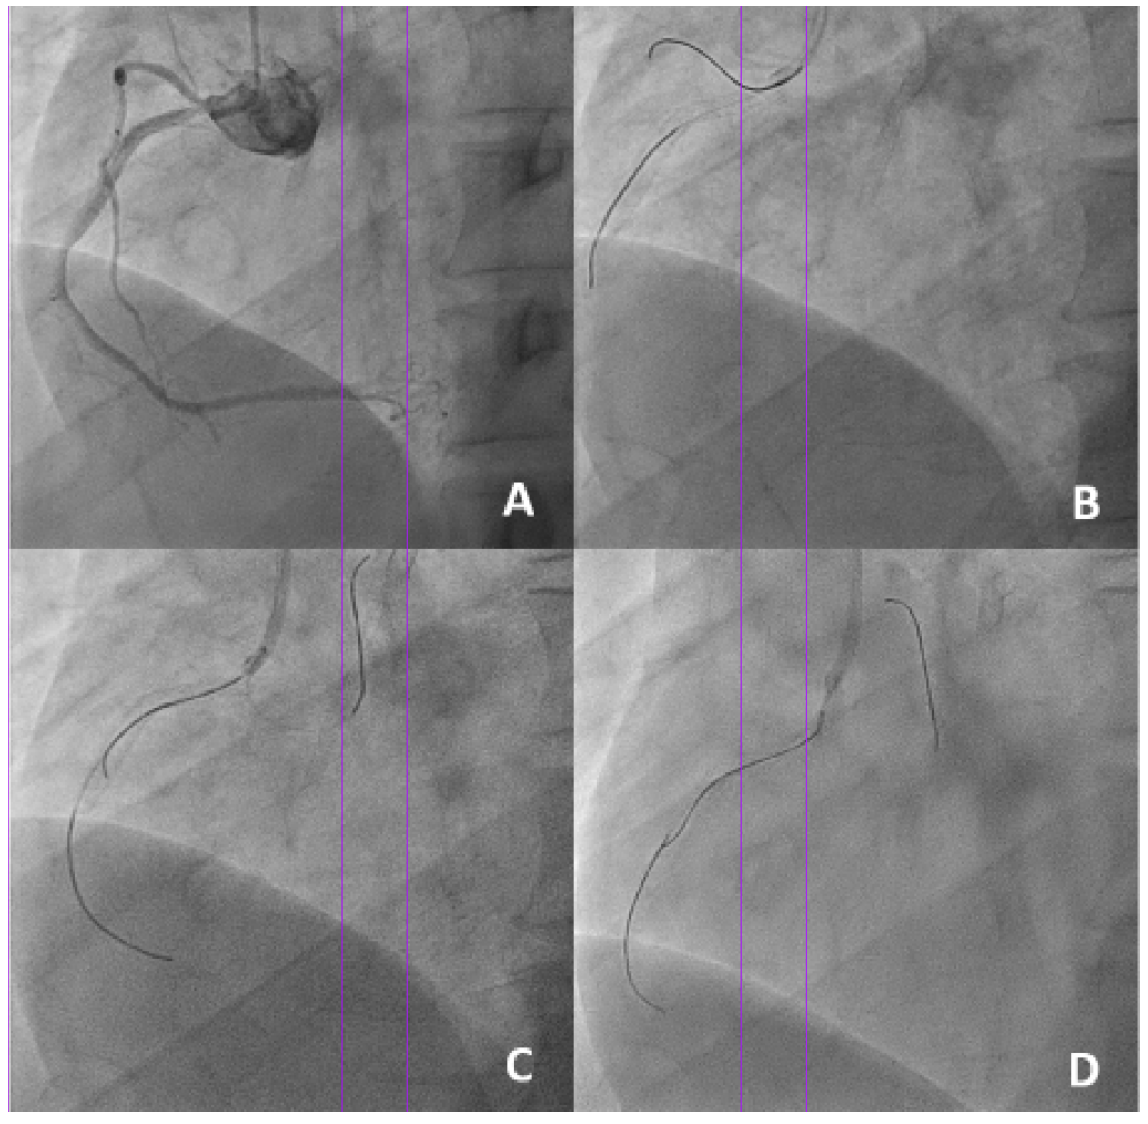

A 56-year-old man with exertional angina underwent coronary angiography, which showed severe restenosis within a previously placed stent in the ostial right coronary artery (RCA). Selective engagement of the RCA with a JR4 diagnostic catheter was difficult due to excessive protrusion of the previous stent into the aorta (Figure 1A). A 6-Fr, JR4 guide catheter was used for intervention.

A workhorse guidewire was able to enter the conus branch through a protruding side-strut. Wiring the RCA proved difficult and could only be done through a protruding side-strut (Figure 1B). A Sasuke dual-lumen catheter (DLC; Asahi Intecc) was loaded onto the RCA guidewire, but the central stent lumen could not be wired successfully (Figure 1C). The DLC was then loaded onto a floating wire, and the central stent lumen was successfully accessed with a second guidewire (Figure 1D; Video Series).